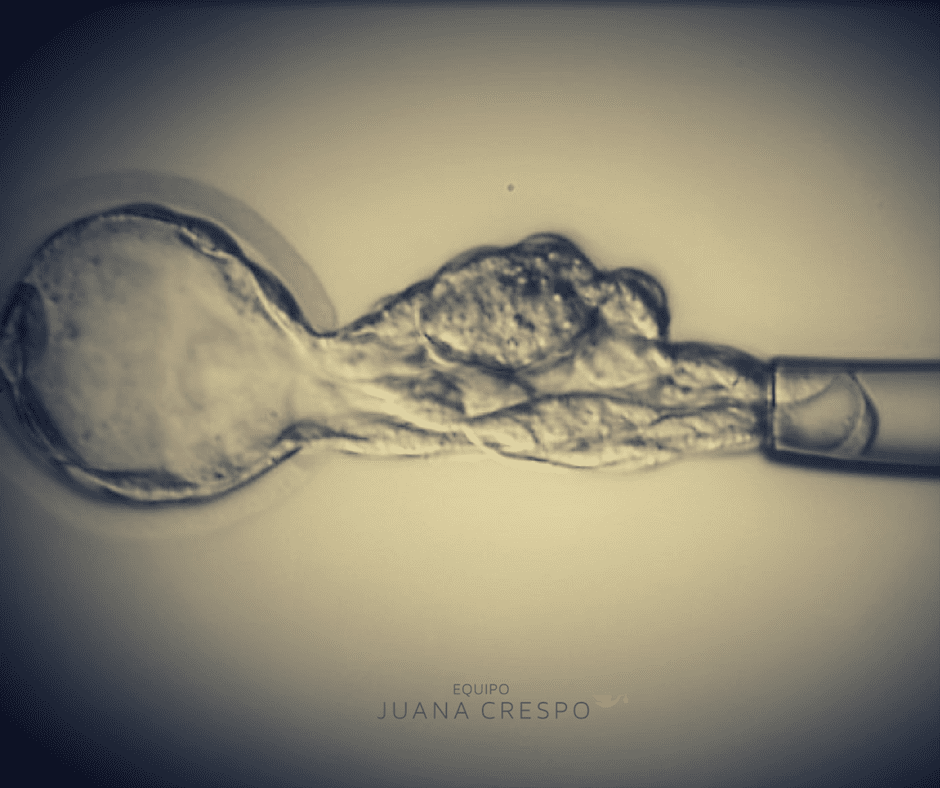

¿Por qué elegir una clínica especializada en alta complejidad reproductiva?

La búsqueda de un embarazo puede llegar a ser un proyecto largo y lleno de incertidumbre, sobre todo cuando el resultado no llega en el momento esperado. Muchas mujeres y […]